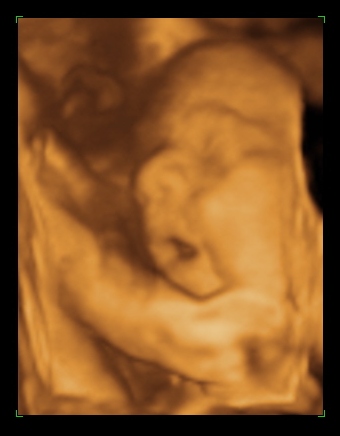

Rólunk: tegnap voltam a dokinál, nagy valószinüséggel kislány a Pötty babánk (de még nem mondta tutira a doki, mert eléggé összezárta a lábikóit)